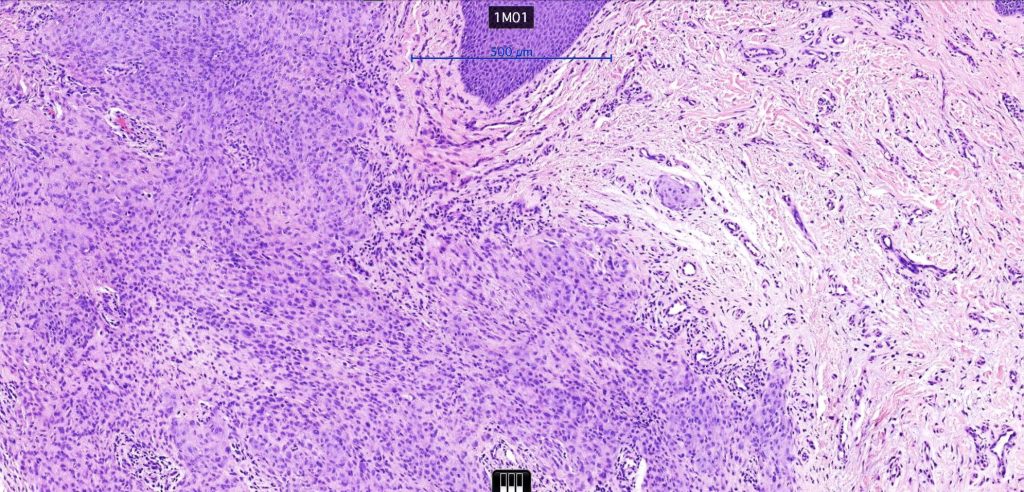

•The epidermis may show a collarette surrounding an often dome-shaped nodule

•Pure population of myoepithelial cells dispersed in sheet-like, reticular, whorled or fascicular patterns in a myxoid or hyaline stroma

•No glandular or ductal differentiation

•No pleomorphism and absent or scanty mitoses